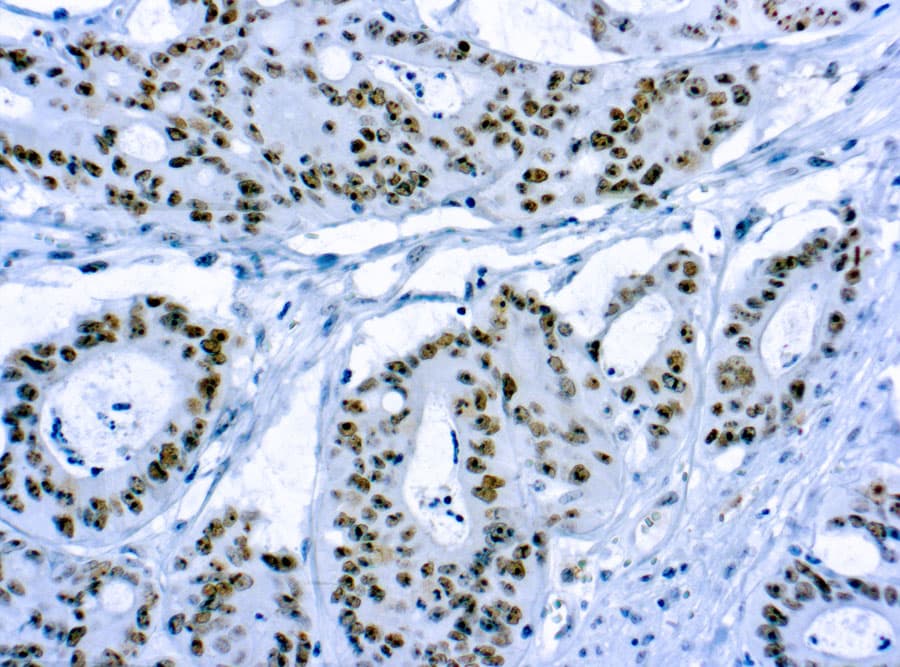

Les anticorps Anti-CD56 (molécule d’adhésion cellulaire neuronale, NCAM) CE/IVD pour immunohistochimie (IHC) permettent une détection fiable de CD56 dans les tissus fixés au formol et inclus en paraffine (FFPE), facilitant un immunophénotypage précis en hématopathologie. CD56 est une glycoprotéine transmembranaire de la superfamille des immunoglobulines, avec plusieurs isoformes (NCAM 120, NCAM 140, NCAM 180) qui diffèrent par la longueur de leur domaine intracellulaire et leur distribution tissulaire. Elle est principalement exprimée par les cellules NK et certaines sous-populations de lymphocytes T, avec également une expression observée dans certains types cellulaires néoplasiques.

- Lymphomes à cellules NK et néoplasmes associés : L’IHC CD56 constitue un marqueur clé pour une classification précise.

- Pathologies des plasmocytes : Une expression anormale de CD56 dans le myélome multiple aide à confirmer la prolifération clonale des plasmocytes et peut être corrélée à des paramètres cliniques ou pronostiques.

- Sous-typage des leucémies : Observée dans certains sous-types de leucémie myéloïde aiguë, elle aide à la sous-classification lorsqu’elle est utilisée en combinaison avec la morphologie et d’autres marqueurs immunophénotypiques.